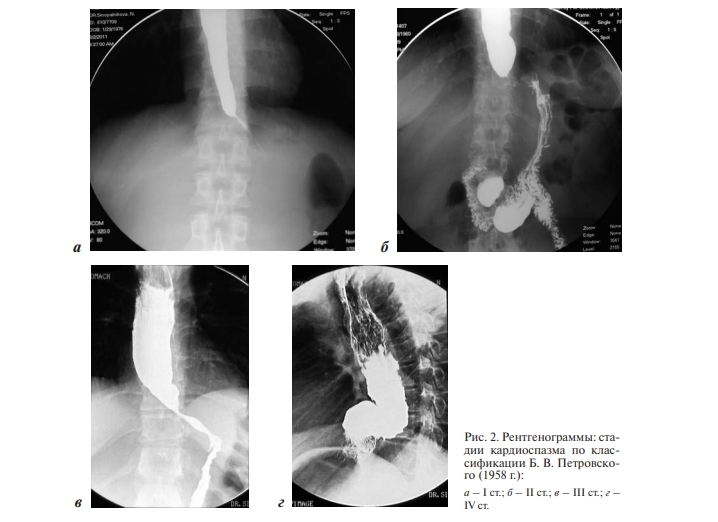

Кардиоспазм лечение

Кардиоспазм лечение 113 фотографий